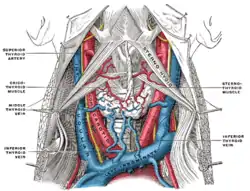

The fascia and middle thyroid veins. (Middle thyroid vein labeled at center left.) | |